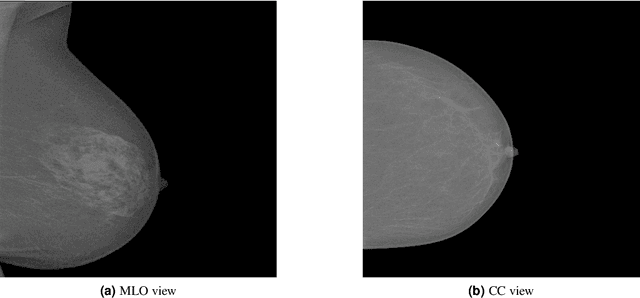

Abstract:Mammography is the most widely used gold standard for screening breast cancer, where, mass detection is considered as the prominent step. Detecting mass in the breast is, however, an arduous problem as they usually have large variations between them in terms of shape, size, boundary, and texture. In this literature, the process of mass detection is automated with the use of transfer learning techniques of Deep Convolutional Neural Networks (DCNN). Pre-trained VGG19 network is used to extract features which are then followed by bagged decision tree for features selection and then a Support Vector Machine (SVM) classifier is trained and used for classifying between the mass and non-mass. Area Under ROC Curve (AUC) is chosen as the performance metric, which is then maximized during classifier selection and hyper-parameter tuning. The robustness of the two selected type of classifiers, C-SVM, and \u{psion}-SVM, are investigated with extensive experiments before selecting the best performing classifier. All experiments in this paper were conducted using the INbreast dataset. The best AUC obtained from the experimental results is 0.994 +/- 0.003 i.e. [0.991, 0.997]. Our results conclude that by using pre-trained VGG19 network, high-level distinctive features can be extracted from Mammograms which when used with the proposed SVM classifier is able to robustly distinguish between the mass and non-mass present in breast.